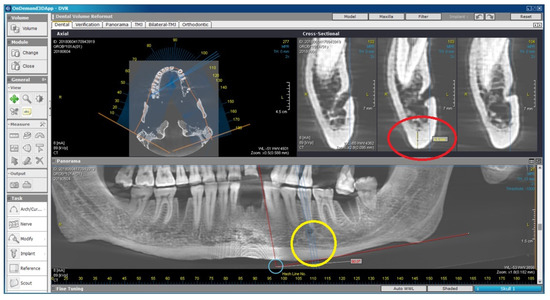

2.2. Radiomorphometric Assessments